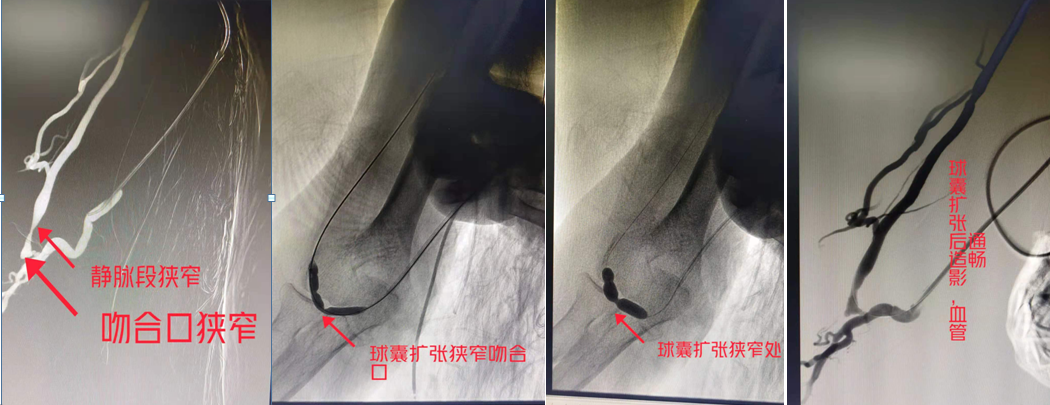

(上图造影可见自体动静脉吻合口处明显狭窄、静脉段狭窄明显,球囊依次扩张吻合口狭窄处及静脉段狭窄处,再次造影可见狭窄明显改善)